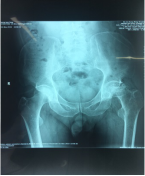

11月份门诊诊疗病例80余人次,病种大多为颈椎病、腰椎间盘突出症、腰椎管狭窄症、梨状肌紧张综合征、胸腰椎小关节紊乱症、小儿髋关节滑膜崁顿、膝关节骨性关节炎、膝关节滑膜炎、肩关节周围炎、股骨头坏死、距骨坏死及桡骨远端骨折、锁骨骨折、尺骨鹰嘴骨折、尺骨骨折、股骨颈骨折、股骨大粗隆撕脱骨折、踝关节骨折、掌骨骨折、指骨骨折、跖骨骨折、趾骨骨折、肩关节脱位等。